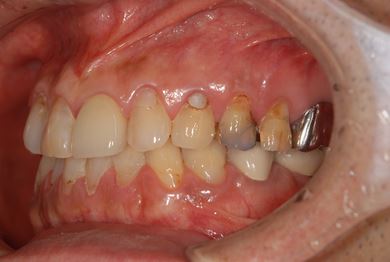

| 性別/年齢 | 男性 / 69歳 | ||||||||||||||||||||||||||||||||

| 主訴 | 1.左上奥歯の詰め物が取れた 2.左上前歯の欠け 3.右下奥歯の欠け | ||||||||||||||||||||||||||||||||

| 治療方針 | セラミック治療にて、審美的回復を行う。 | ||||||||||||||||||||||||||||||||

| 治療内容 | メタルボンドセラミッククラウン1本(メタルボンド用土台1本)、ハイブリッドセラミックインレー1本 | ||||||||||||||||||||||||||||||||